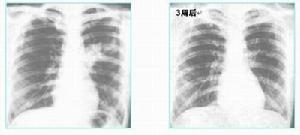

多重肺部感染感染前後比較

1.臨床疾病譜多重感染常見於吸入性肺炎和肺膿腫、支氣管擴張症、醫院內肺炎特別是呼吸機相關性肺炎、免疫受損害宿主肺炎和其他各種重症肺炎。